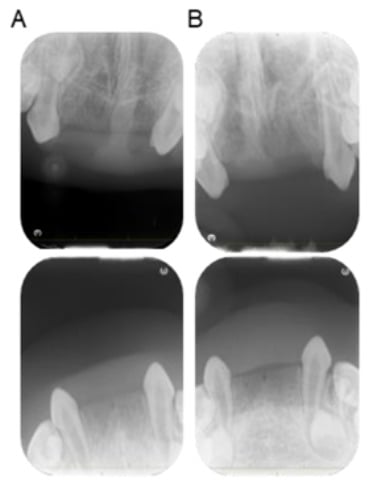

2. Case Presentation